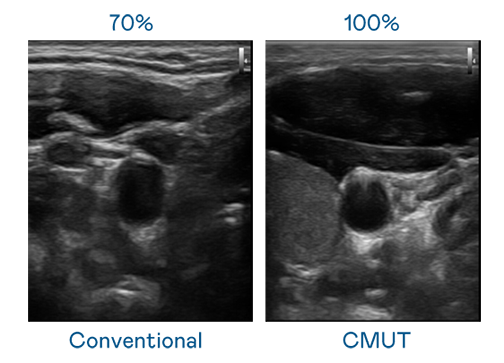

CMUT 技术是一种用电容式微机电元件来产生超音波讯号的技术。与传统 PZT 压电式技术相比,CMUT 频宽增加 30%,更宽频的超音波讯号让影像解析度大幅提升,是实现高影像品质医疗超音波扫描、促进精准医疗发展的关键技术。

大频宽带来超清晰影像

超音波影像的解析度高低,首先取决于探头能发出的讯号频宽。AG真人平台 CMUT 可提供高清晰的超音波讯号,提供高频宽、高灵敏度、影像纹理细节更高的超音波影像,协助医护人员缩短影像判读时间及利用精准的医疗影像进行诊断。